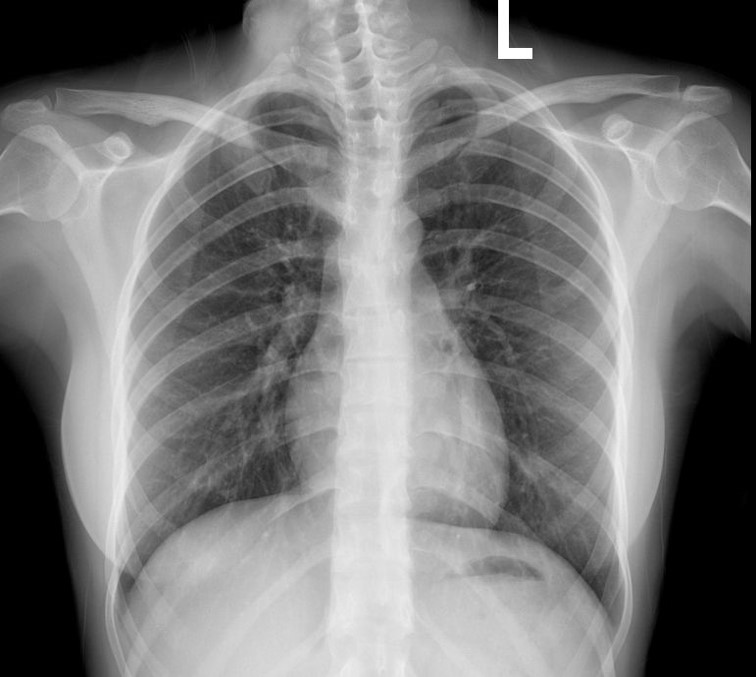

胸片检查所见:

胸廓骨骼及胸壁软组织未见异常。纵膈及器官中未见移位。

纵膈未见增宽

主动脉

无异常,心脏形态大小未见异常。

肺门形态大小未见异常。

两膈光整,两肋膈角锐利。

两肺野清晰,纹理结构清楚,未见异常密度。

印象:胸部未见明显异常。